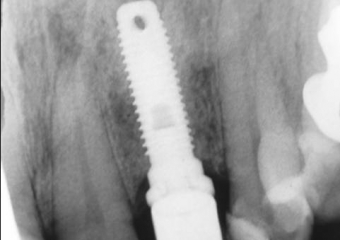

Rx atual (2009) de Implantes Nobel® e Próteses Instaladas nos elementos 12 e22, em 1998